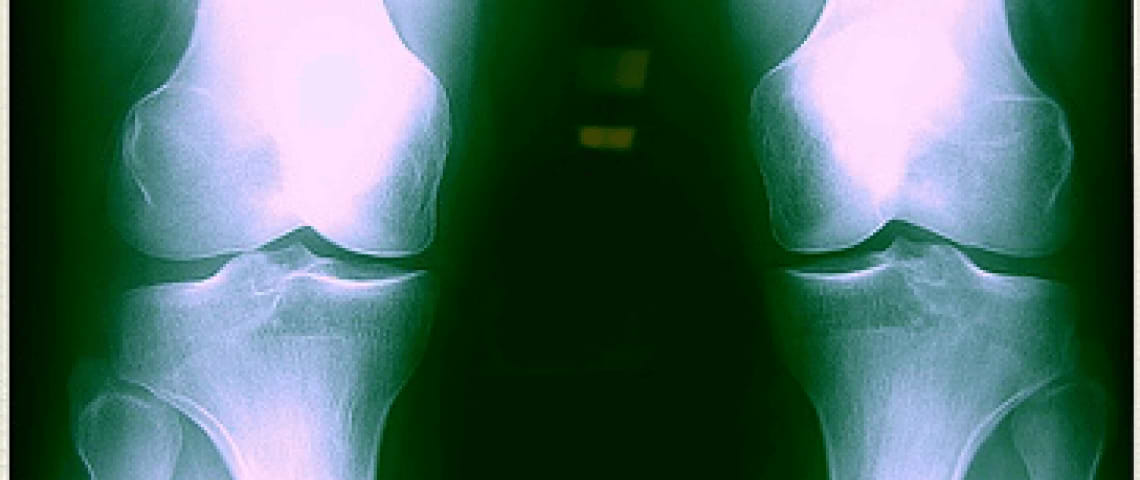

NEWS FLASH: Calcium is not the only mineral in bone, despite the dairy industry wanting us to believe so. Yes it is important, but your bones are composed o